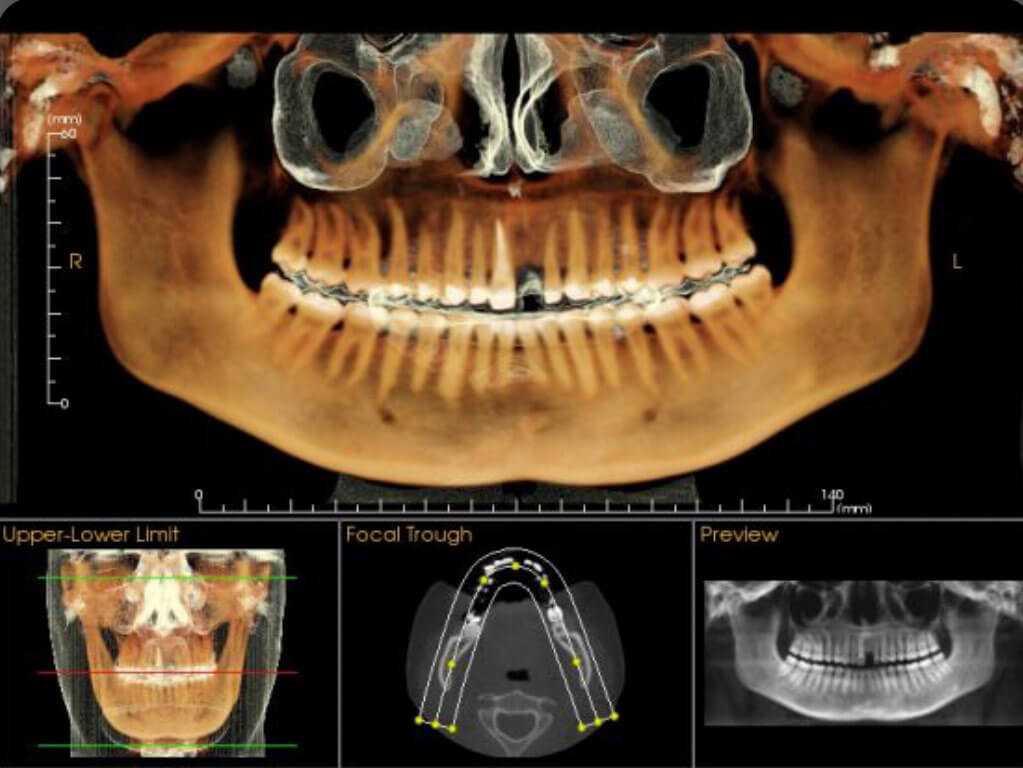

It’s basically a three-dimensional radiograph, a “3D x-ray”. CBCT stands for “Cone Beam Computed Tomography”. You may have heard of a medical “CAT scan”; this is a similar technology, but using a cone-shaped beam allows us to get the information we need with significantly less radiation.

Dentists will prescribe a CBCT scan for a number of reasons. Sometimes we want to see a 3D image prior to surgery or implant placement for your safety. Other times we need to see the jaw joints, sinuses, or some unusual anatomy.